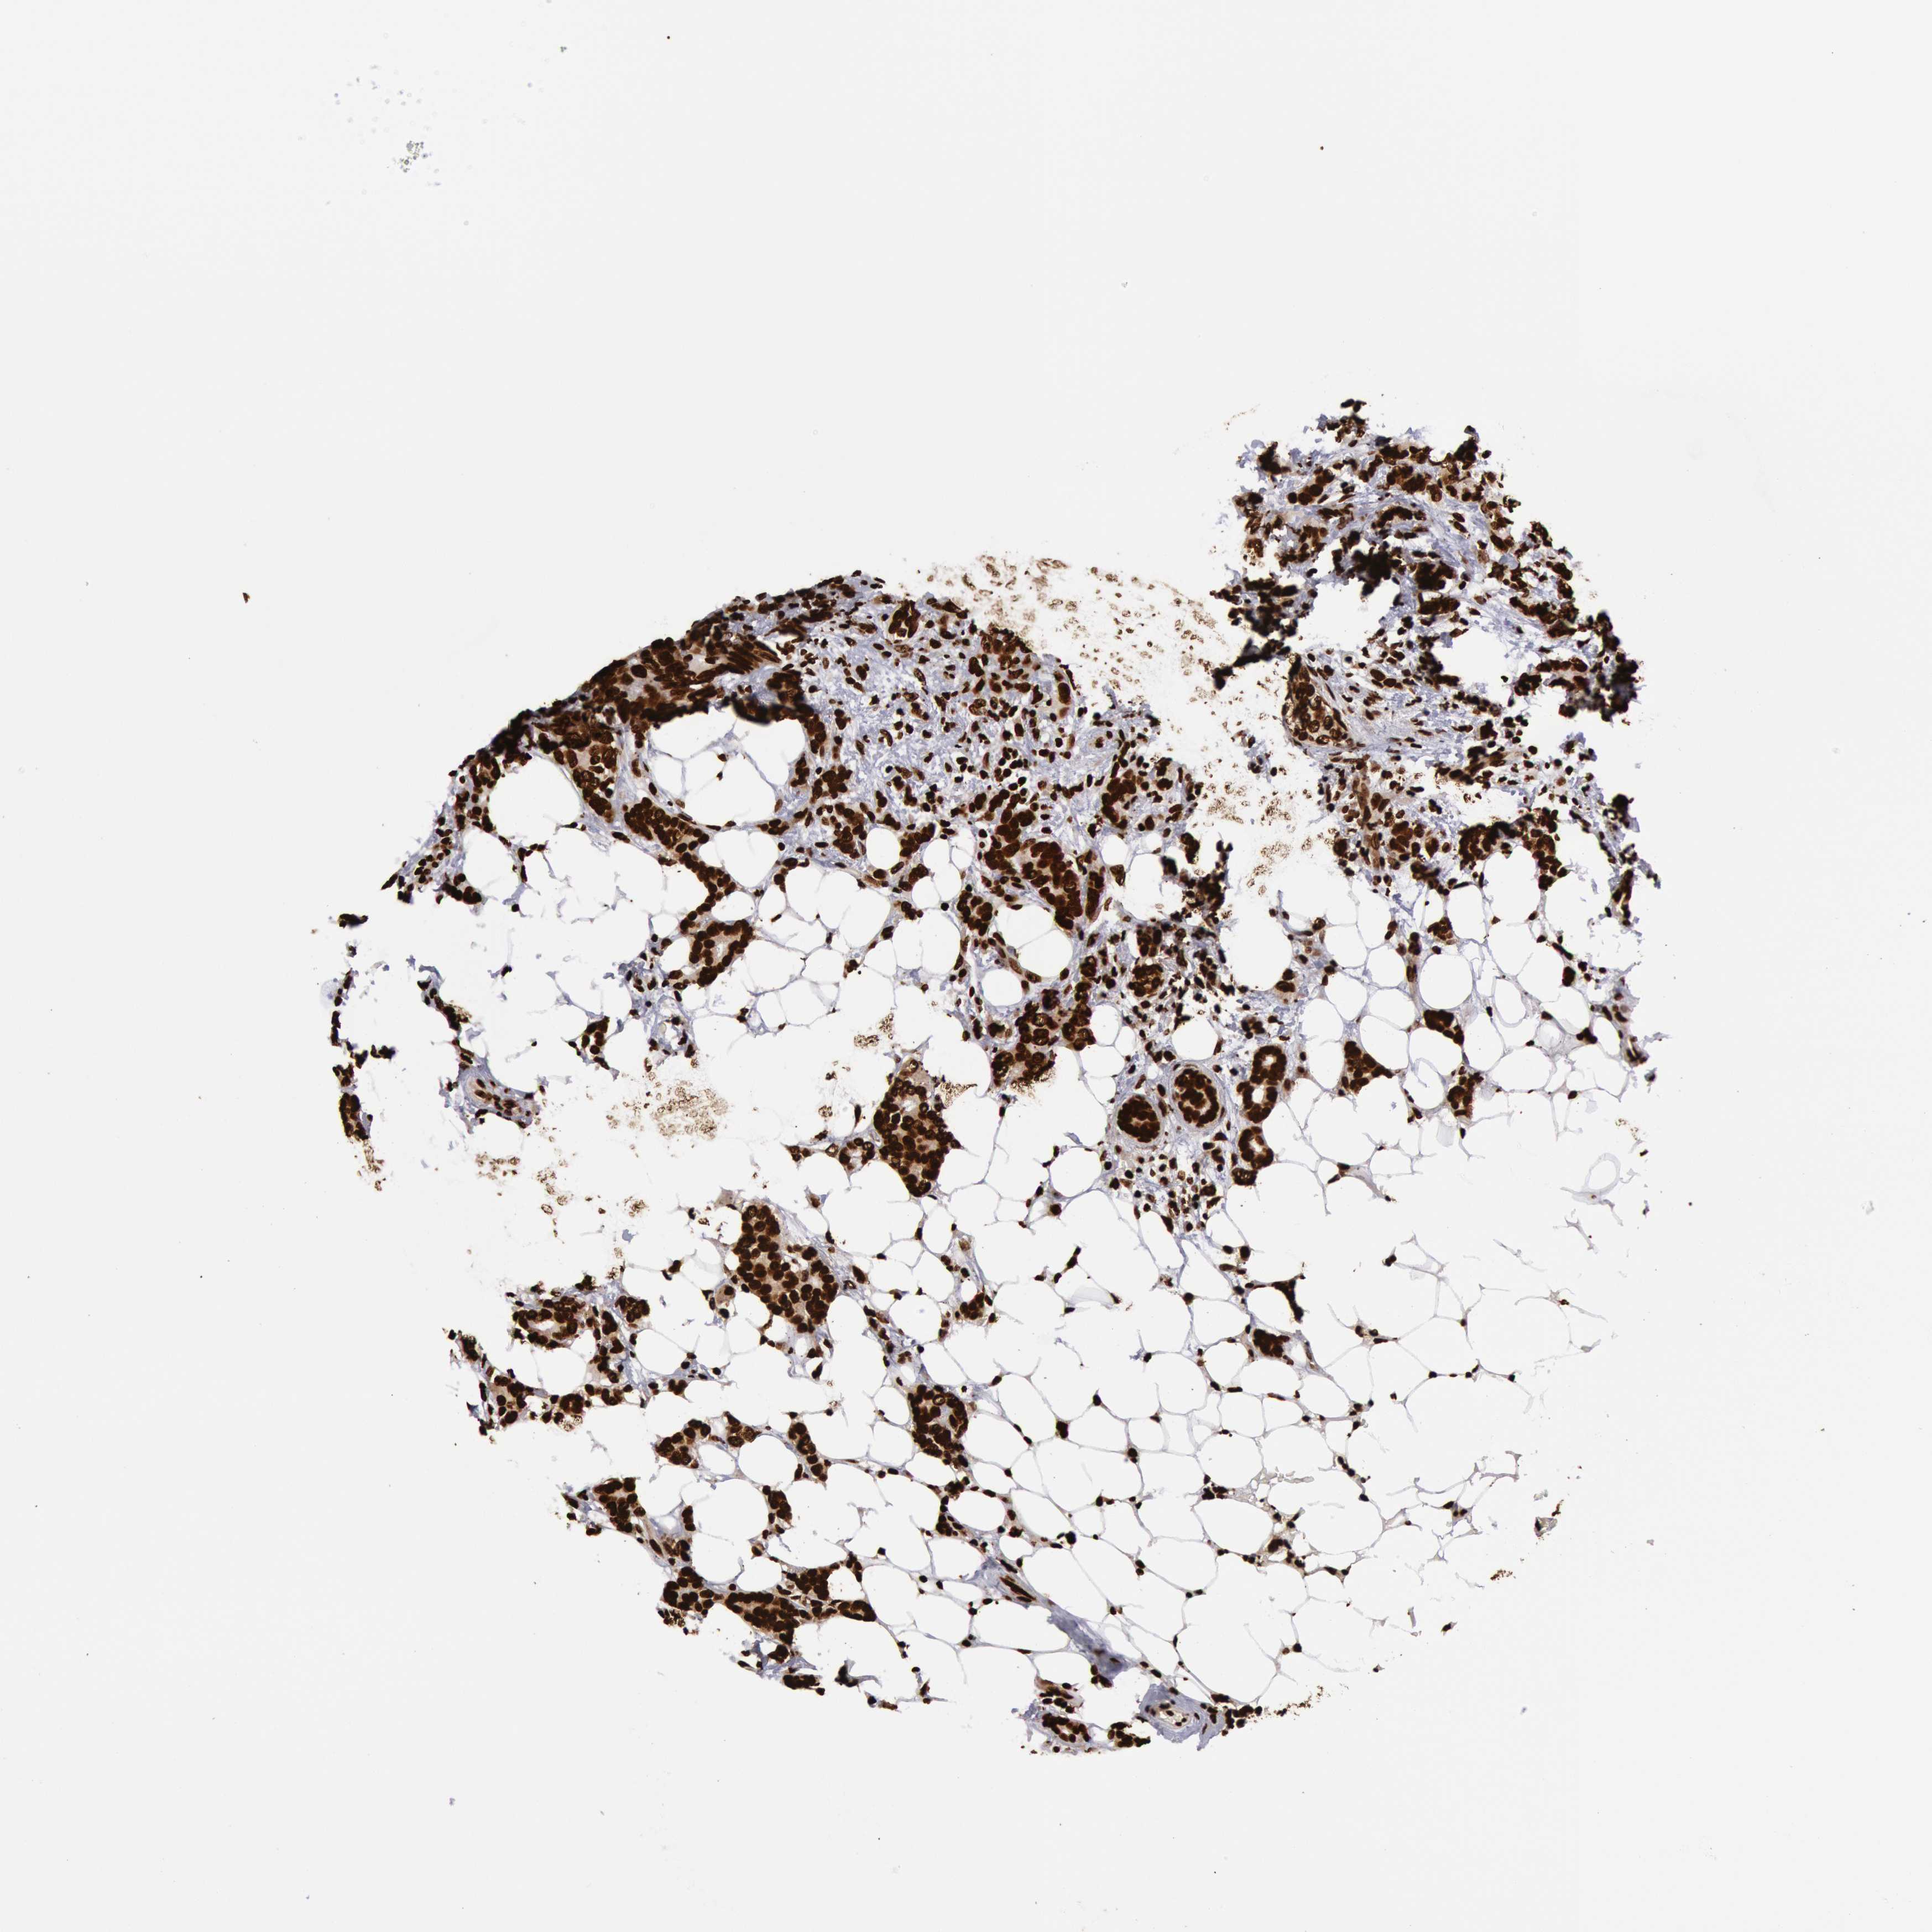

CANCER BREAST CANCER Show tissue menu

BRCA TCGA BRCA VALIDATION PROTEIN EXPRESSION